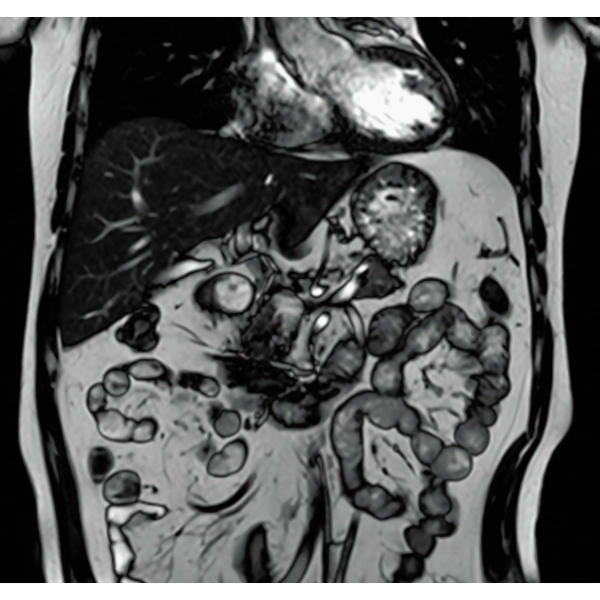

"DLR" is applicable to all body parts and promotes high speed imaging and diagnostic efficiency

IP-RAPID x DLR Plus can also shorten imaging time, allowing more images to be taken in the same examination time.

Additional imaging, such as different image types and cross sections, can be added to the conventional examination to increase the amount of information and make the diagnosis more reliable.

IP-RAPID x DLR Plus gives you the flexibility to shorten respiratory gated series or even replace them with breath-holds, depending on the patient’s situation. This gives you more options and a wider range of examinations to choose from.

IP-RAPID x DLR Plus can be used for basic imaging such as VolumeScan, RadialScan, HalfScan, and many other imaging methods such as MultiContrastScan FatSep and DWI.

It can also be used with time-consuming scans such as Whole Body DWI and Whole Spine imaging, providing more detailed information in many areas than previously possible.